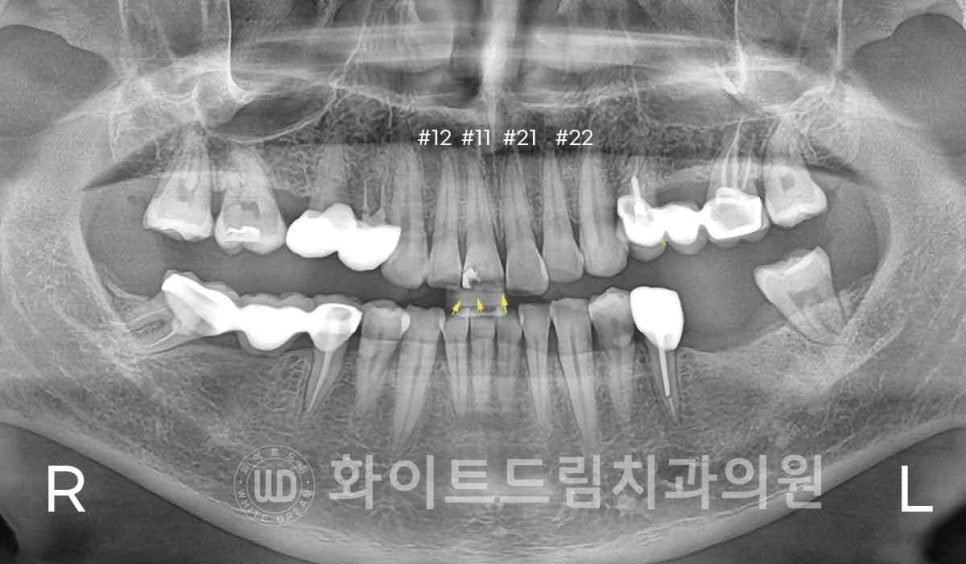

치아 표면에 실금이 많이 가있고, 기존에 앞니 충치치료를 레진으로 받으신 부위도 있는 상태입니다.

게다가 11번 치아에 설측면(혀쪽 방향의 치아 면, lingual) 충치,

21번 치아는 옆 22번 치아와 맞닿는 쪽, Distal 방향으로 충치가 발생한

상태였습니다.

11번 앞니는 충치의 범위가 크고, 치아의 깨짐으로 길이가 짧아진 상태였기 때문에

올 세라믹 크라운 치료를 진행하는 것을 권해드렸으나,

옆 치아들과 동일한 라미네이트로 치료를 받길 원하셔서

앞니 4개를 당일 라미네이트로 치료하기로 환자분과 상의 후 결정하였답니다.